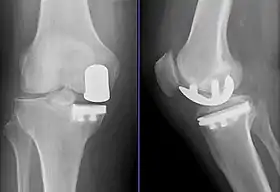

Radiographs of a knee arthroplasty of the medial compartment

Unicompartmental knee arthroplasty (UKA) is a surgical procedure used to relieve arthritis in one of the knee compartments in which the damaged parts of the knee are replaced. UKA surgery may reduce post-operative pain and have a shorter recovery period than a total knee replacement procedure,[1][2] particularly in people over 75 years of age.[3] Moreover, UKAs may require a smaller incision, less tissue damage, and faster recovery times.[2]